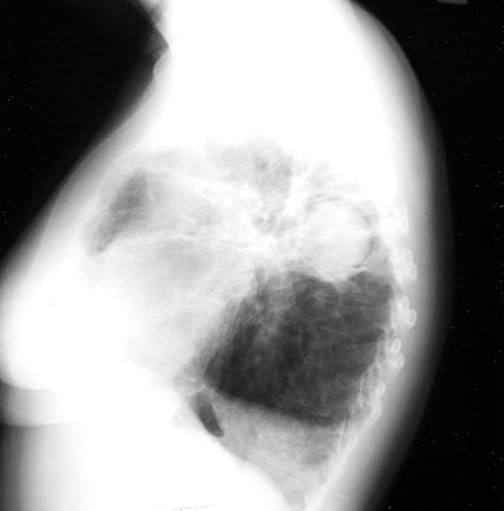

Halo Sign

In a cavity with a fungus ball, there is a crescentic lucent space along the upper portion of the density giving the appearance of a halo. This phenomenon is seen with two clinical presentations of pulmonary aspergillosis:

• Fungous ball  (as in this case)

• Necrotizing subacute pneumonia during recovery phase from leukopenic episodes